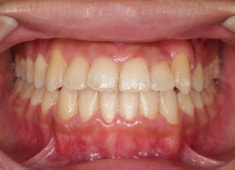

解説:残存している左上乳犬歯Cを抜歯し、そのスペースに左上3番を誘導しました。Cと犬歯ではスペースが足りないので、前歯をアドバンスさせ、反対咬合を同時に解消しております。

治療前

治療後(2年1ヶ月後)

下顎の右側への偏位は解消されました。